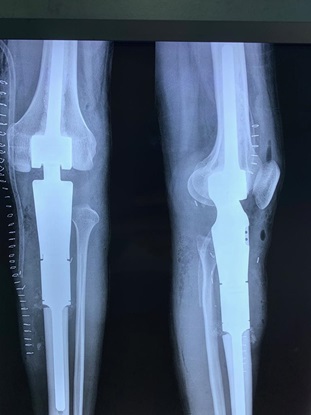

Children and adults with tumors and tumor-like disorders of the bone and soft tissue, such as bone metastases, sarcomas, benign and malignant tumors of the bone or soft tissue, and pathologic fractures, are treated by the Division of Orthopaedic Oncology, which provides them with the highest quality care.

Orthopedic oncology, also known as Musculoskeletal Oncology, focuses on the diagnosis and treatment of both benign and malignant bone tumors, along with other unusual lesions affecting the musculoskeletal system. Bone cancer and soft tissue sarcomas, though rare, demand a comprehensive, multidisciplinary approach to diagnosis and treatment.